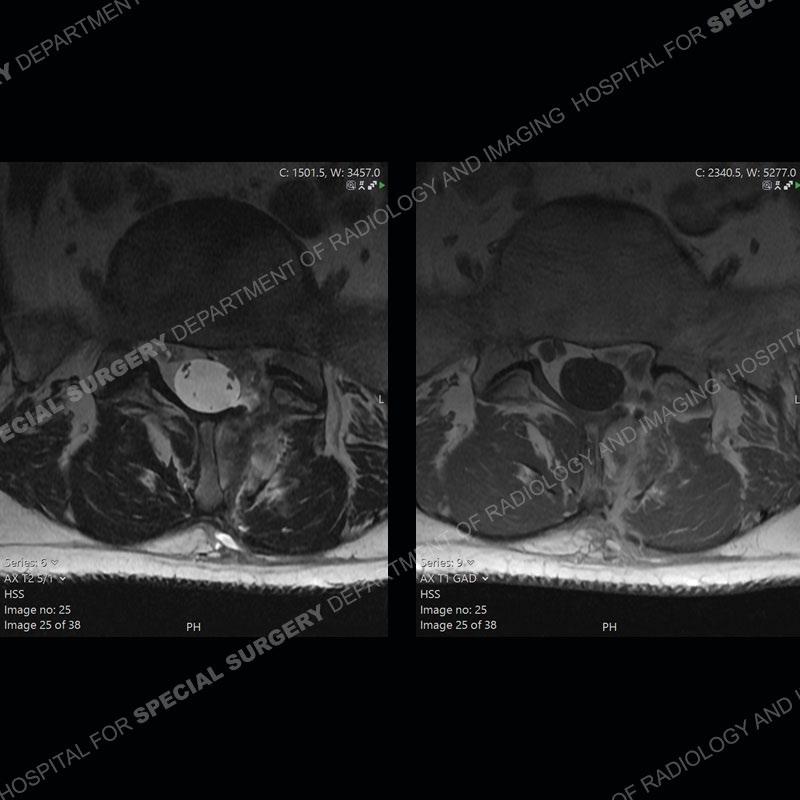

Post operative changes are seen on the left side at L5-S1 where there is near complete removal of the left sided L5 lamina, partial resection of the left L5-S1 facet joint, and resection of the left sided ligamentum flavum. In the anterolateral epidural space about the subarticular recess is a mass that demonstrates similar T1 and T2 signal characteristics to the adjacent degenerated disc. There is enhancement about the periphery of the mass, but the majority of this somewhat geographic or polyploid mass demonstrates no enhancement. The mass exerts prominent mass effect on the left S1 axillary sleeve/proximal nerve root. The left S1 nerve root shows enlargement and increased enhancement as compared to the contralateral right side.

Diagnosis: Recurrent Disc Herniation

Not as much of a diagnostic dilemma as some other cases but more so just a very nice example of what can be a difficult assessment at times. The evaluation of granulation tissue/scar/epidural fibrosis vs. disc herniation particularly in the earlier post operative period can be very difficult. Clues that can assist in identifying a disc herniation are a more geographic or polypoid nature to the mass, signal characteristics similar to the adjacent degenerated disc, mass effect upon the thecal sac/adjacent neural structures, and a typical enhancement pattern. As the disc material is avascular, as long as imaging is performed in a relatively rapid fashion after contrast administration (within 20-30 minutes), the granulation tissue around the disc will enhance but the disc material itself will not. If there is a marked delay between contrast administration and imaging, there may be diffusion of contrast into the disc making the assessment very difficult. The marked utility of contrast to help delineate disc vs. scar has led to our institution employing contrast fairly uniformly within the first two years following surgery.